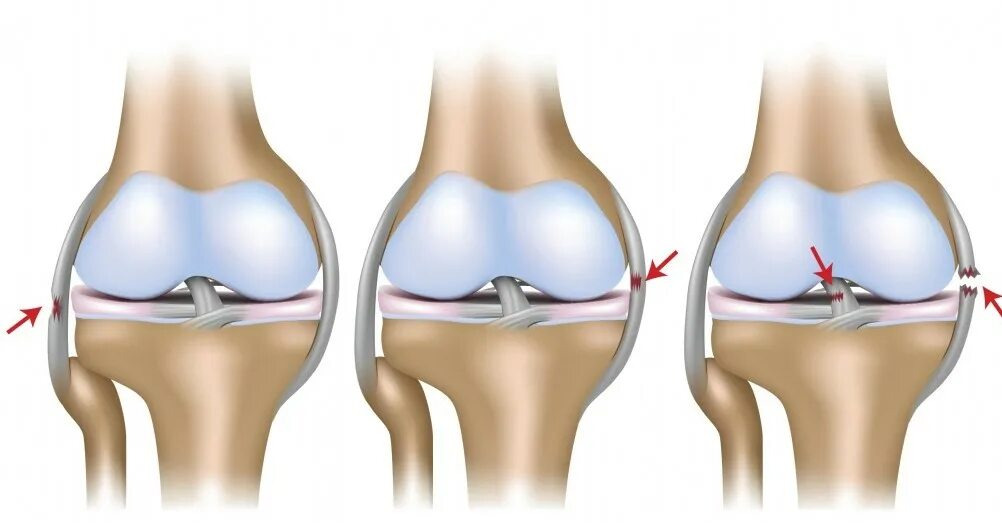

В каком случае меняют сустав